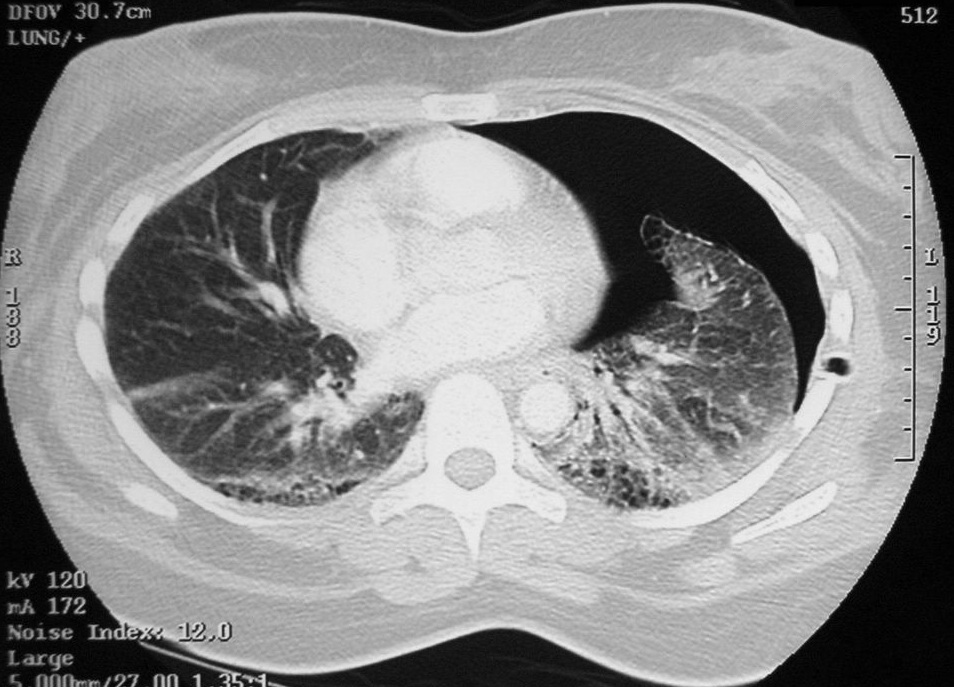

흉부 X선 촬영은 기흉, 폐부종, 폐렴 등을 확인하거나 배제하는 데 유용하다.[22] 조영제를 사용한 나선형 컴퓨터 단층촬영(CT)은 폐색전증을 평가하는 데 사용되는 검사이다.[22]